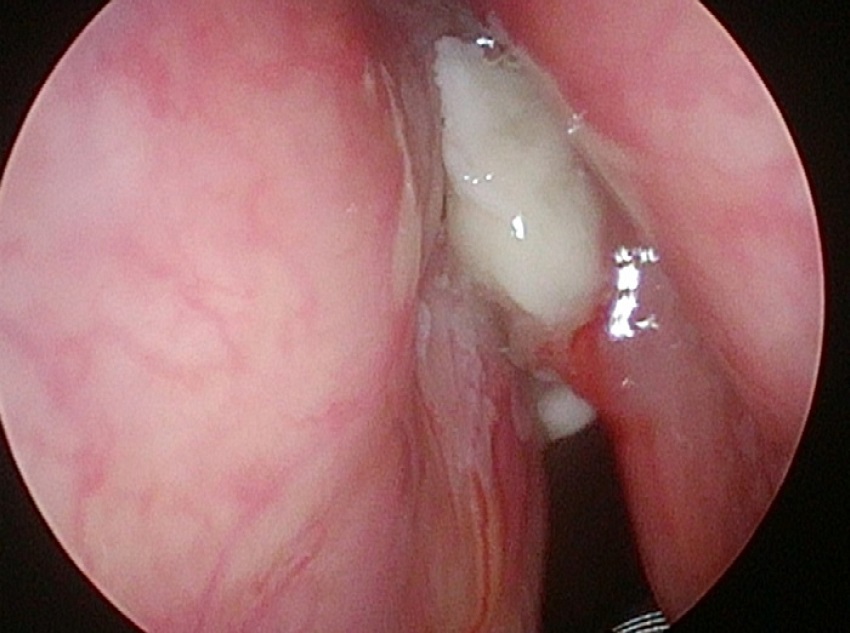

In 6 patients mucosa was suspected only in NBI (Fig. 1), with no such evidence in WL (Fig. 2). In these 6 patients 18/90 (20%) samples were taken. In 5/6 patients 16/18 (88.8%) samples were positive in FS. In 6/18 (33.3%) samples (2 patients) carcinoma, in 10/18 (66.6%) samples (3 patients) severe dysplasia were confirmed. One patient in 2/18 (11.1%) samples had a negative FS.

To summarize, in 6/44 (13.6%) patients NBI allowed to take the FS, so that the diseased mucosa was included into the surgical specimens. Presented analysis showed that sensitivity, specificity and accuracy of WL was 79.5%, 20%, and 71.1% respectively, while NBI corresponding values were: 100%, 0.0%, and 85.7%, respectively.